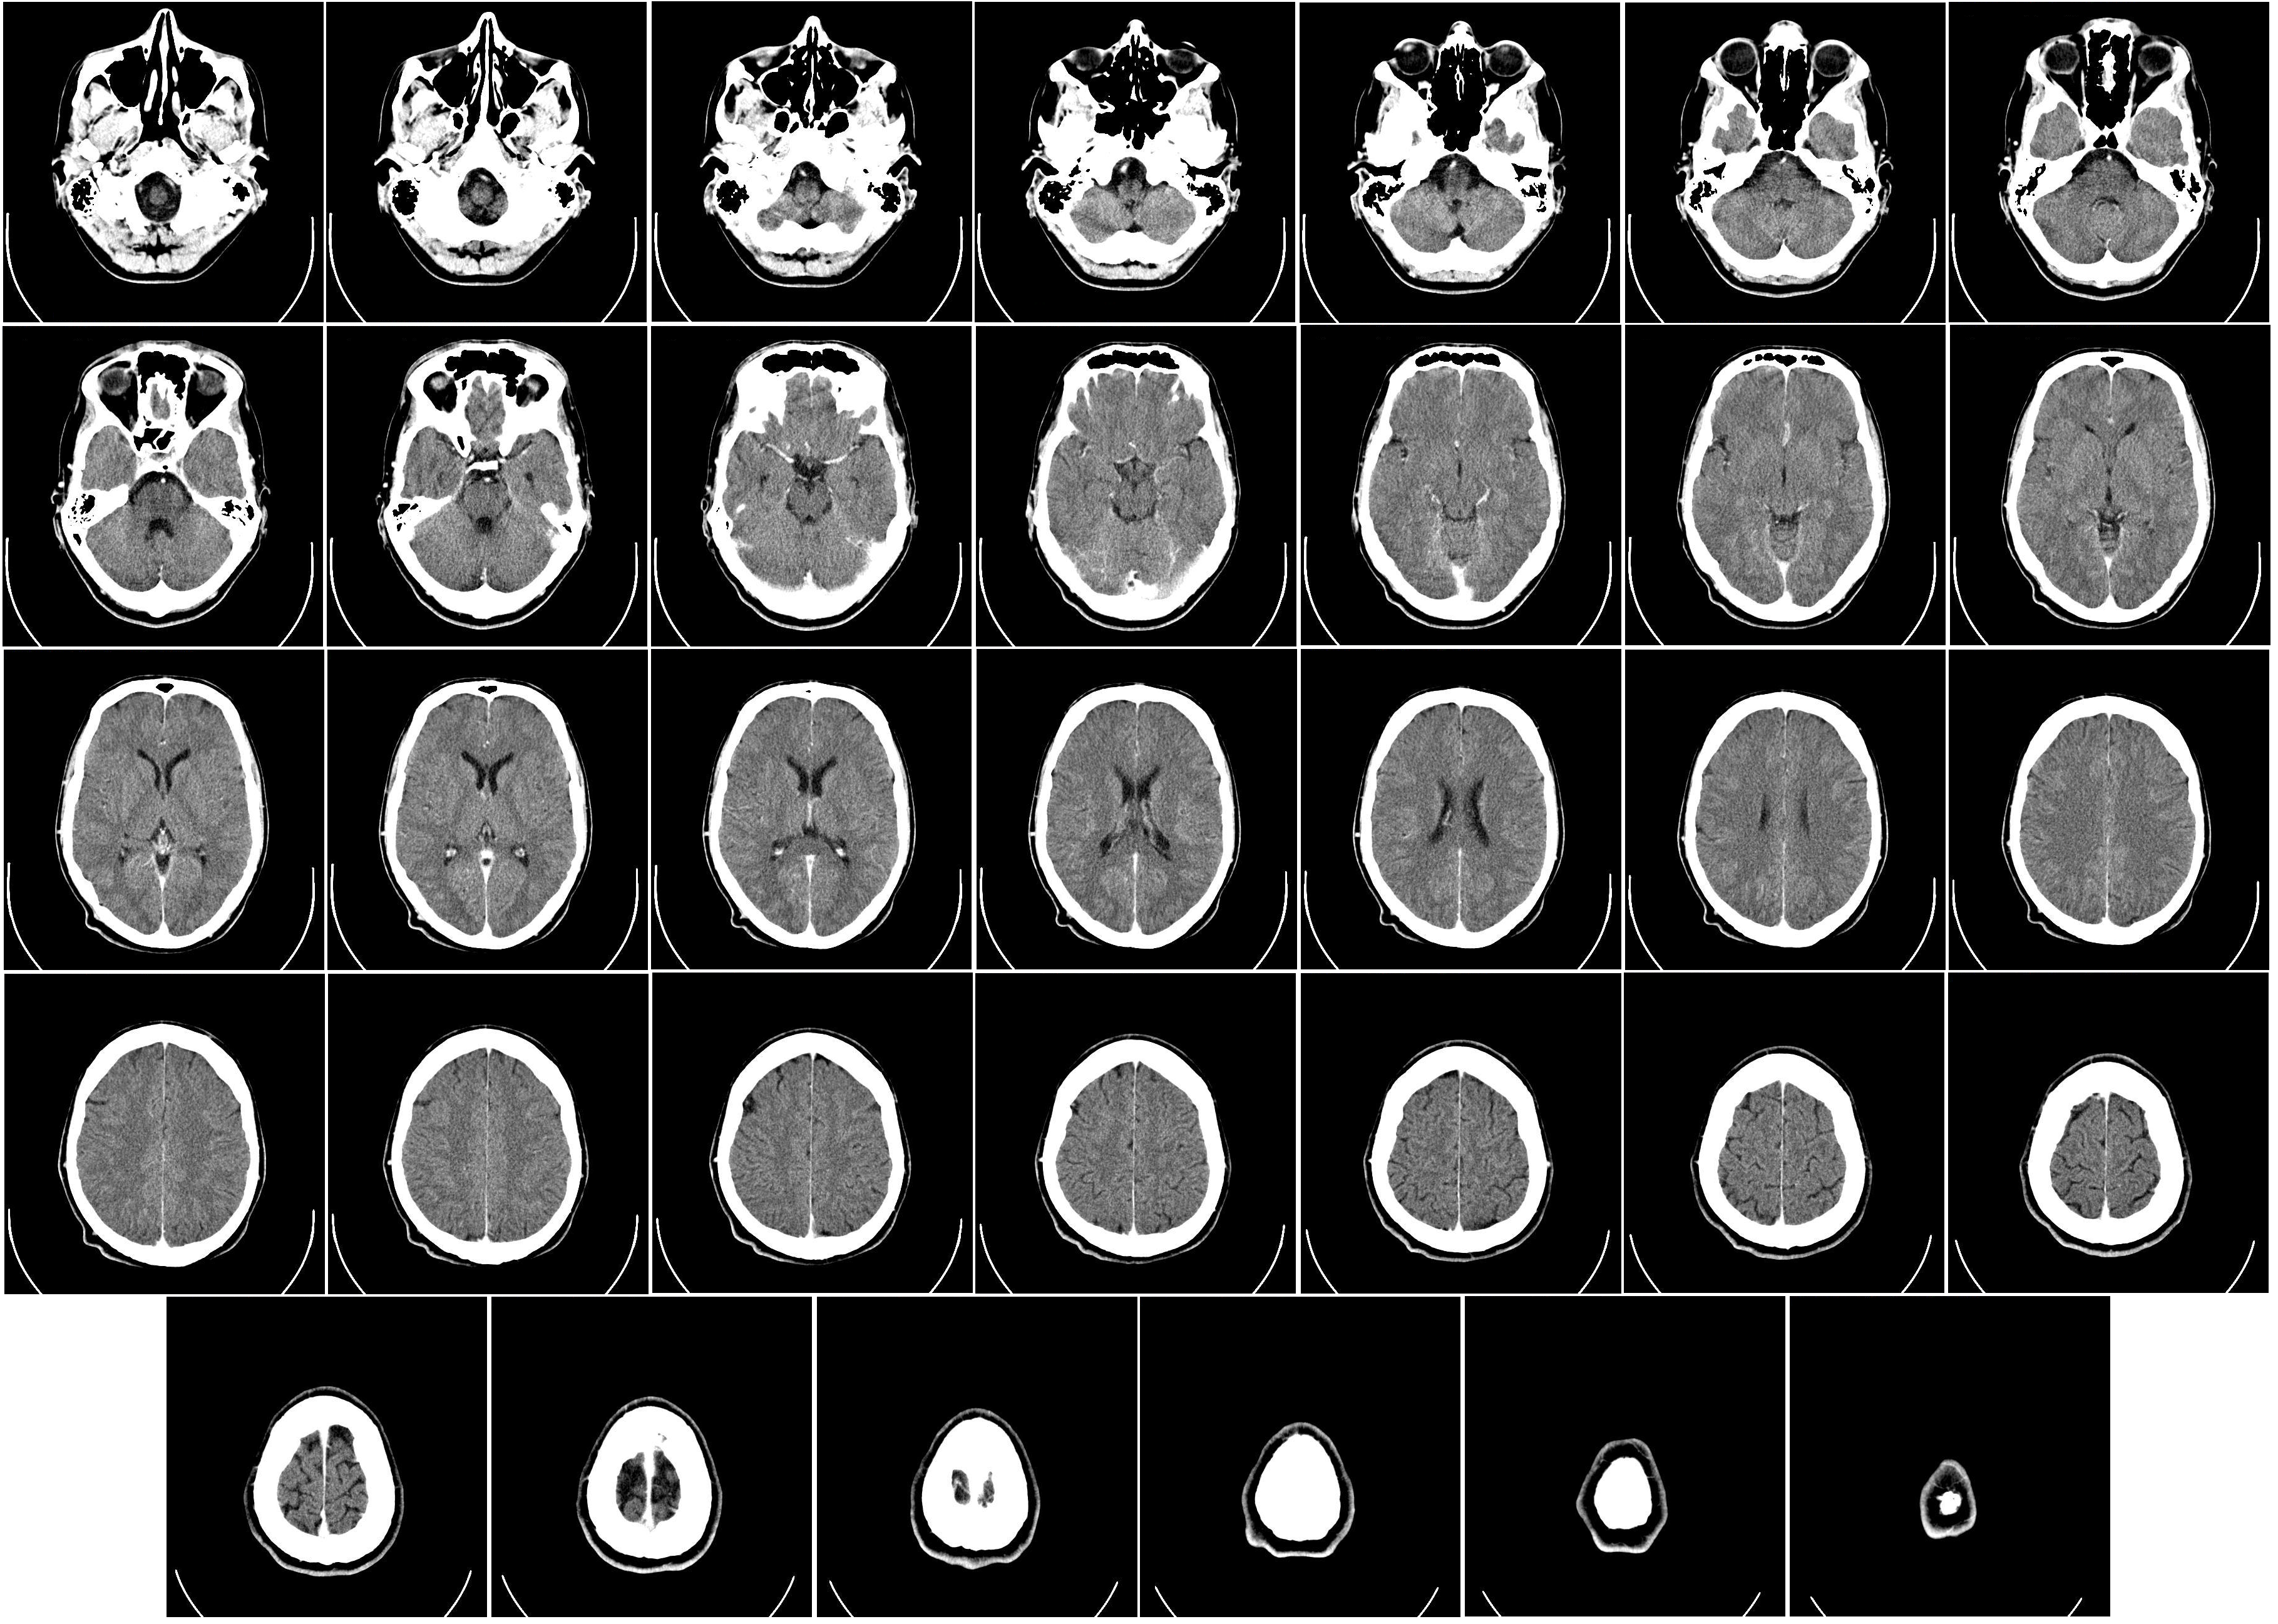

A partir de la década de los 60 del siglo pasado se dieron pasos agigantados en el estudio del cerebro, debido en gran medida a los avances tecnológicos. Por ejemplo, se desarrollaron escáneres que permitieron saber cómo es y cómo funciona este órgano. En años posteriores las investigaciones sobre él fueron enfocadas a la cognición humana (aprendizaje, memoria, percepción, etc.).